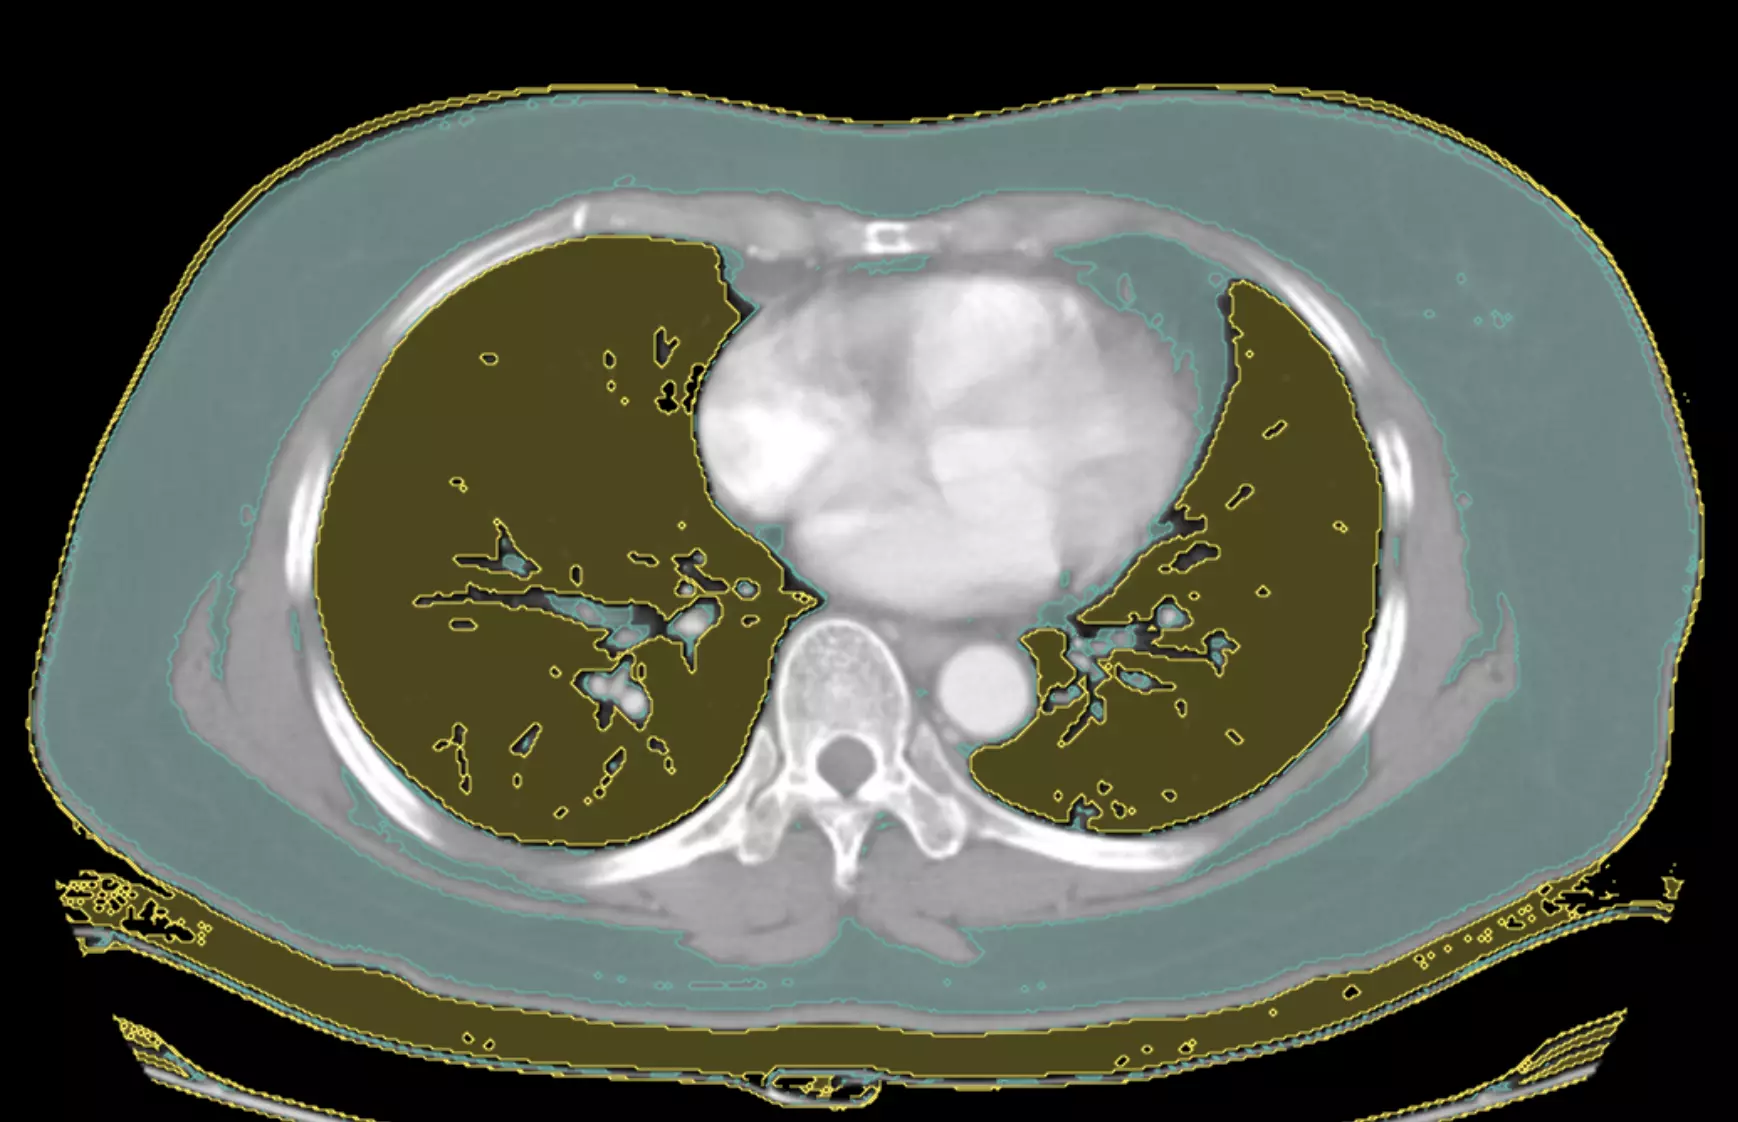

Mask label outputs:

Create 2 mask labels in the UI, one for Fat and one for Lung.